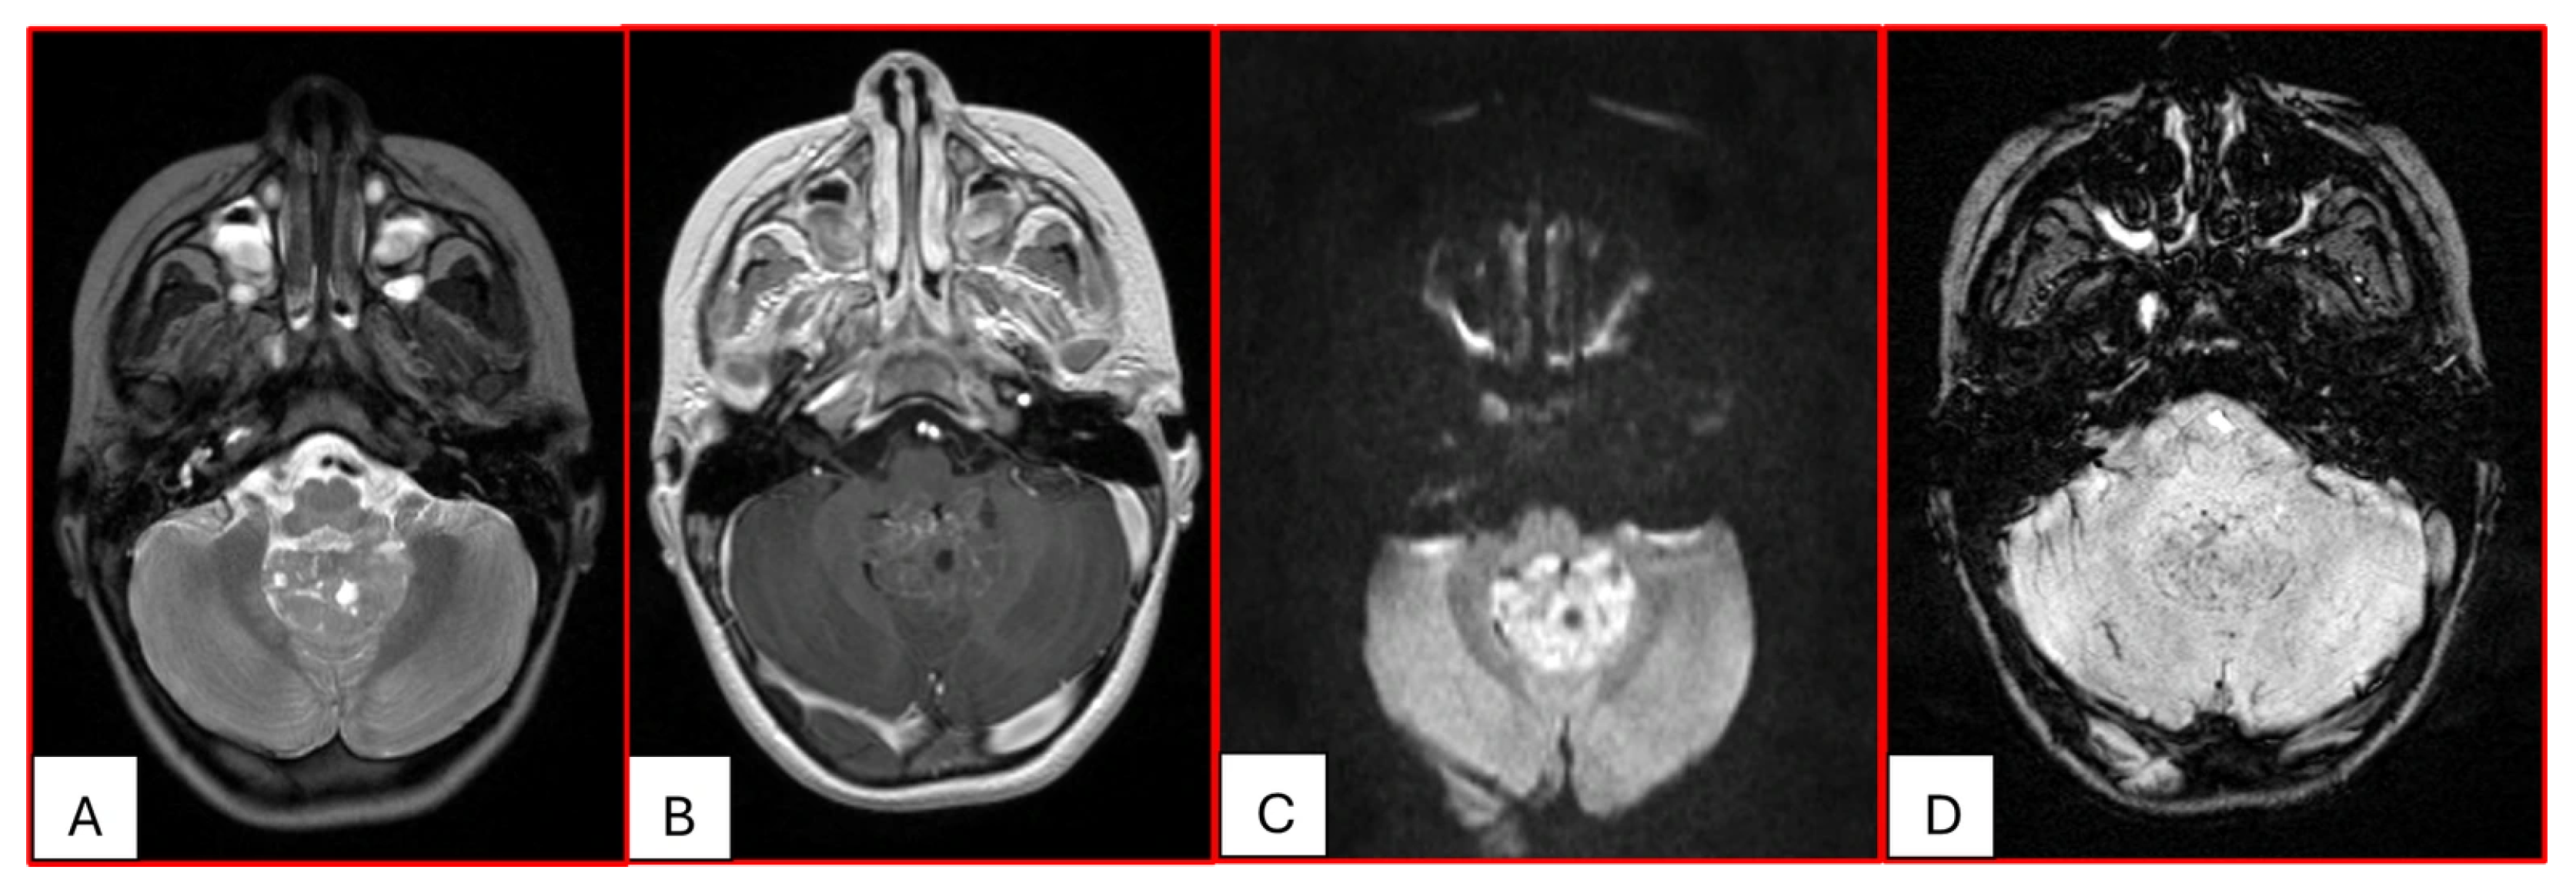

Figure 3. Three-year-old female with ATRT. (A) Axial T2-weighted image shows a mass centered in the midline posterior fossa of heterogeneous intermediate signal with small cystic/necrotic changes. There is no surrounding edema. (B) This mass demonstrates mild heterogeneous enhancement. (C) There is prominent corresponding restricted diffusion. (D) A few foci of susceptibility are noted, which may reflect internal hemorrhage or calcifications. Note that the MRI features of this mass mimic the appearance of Medulloblastoma.